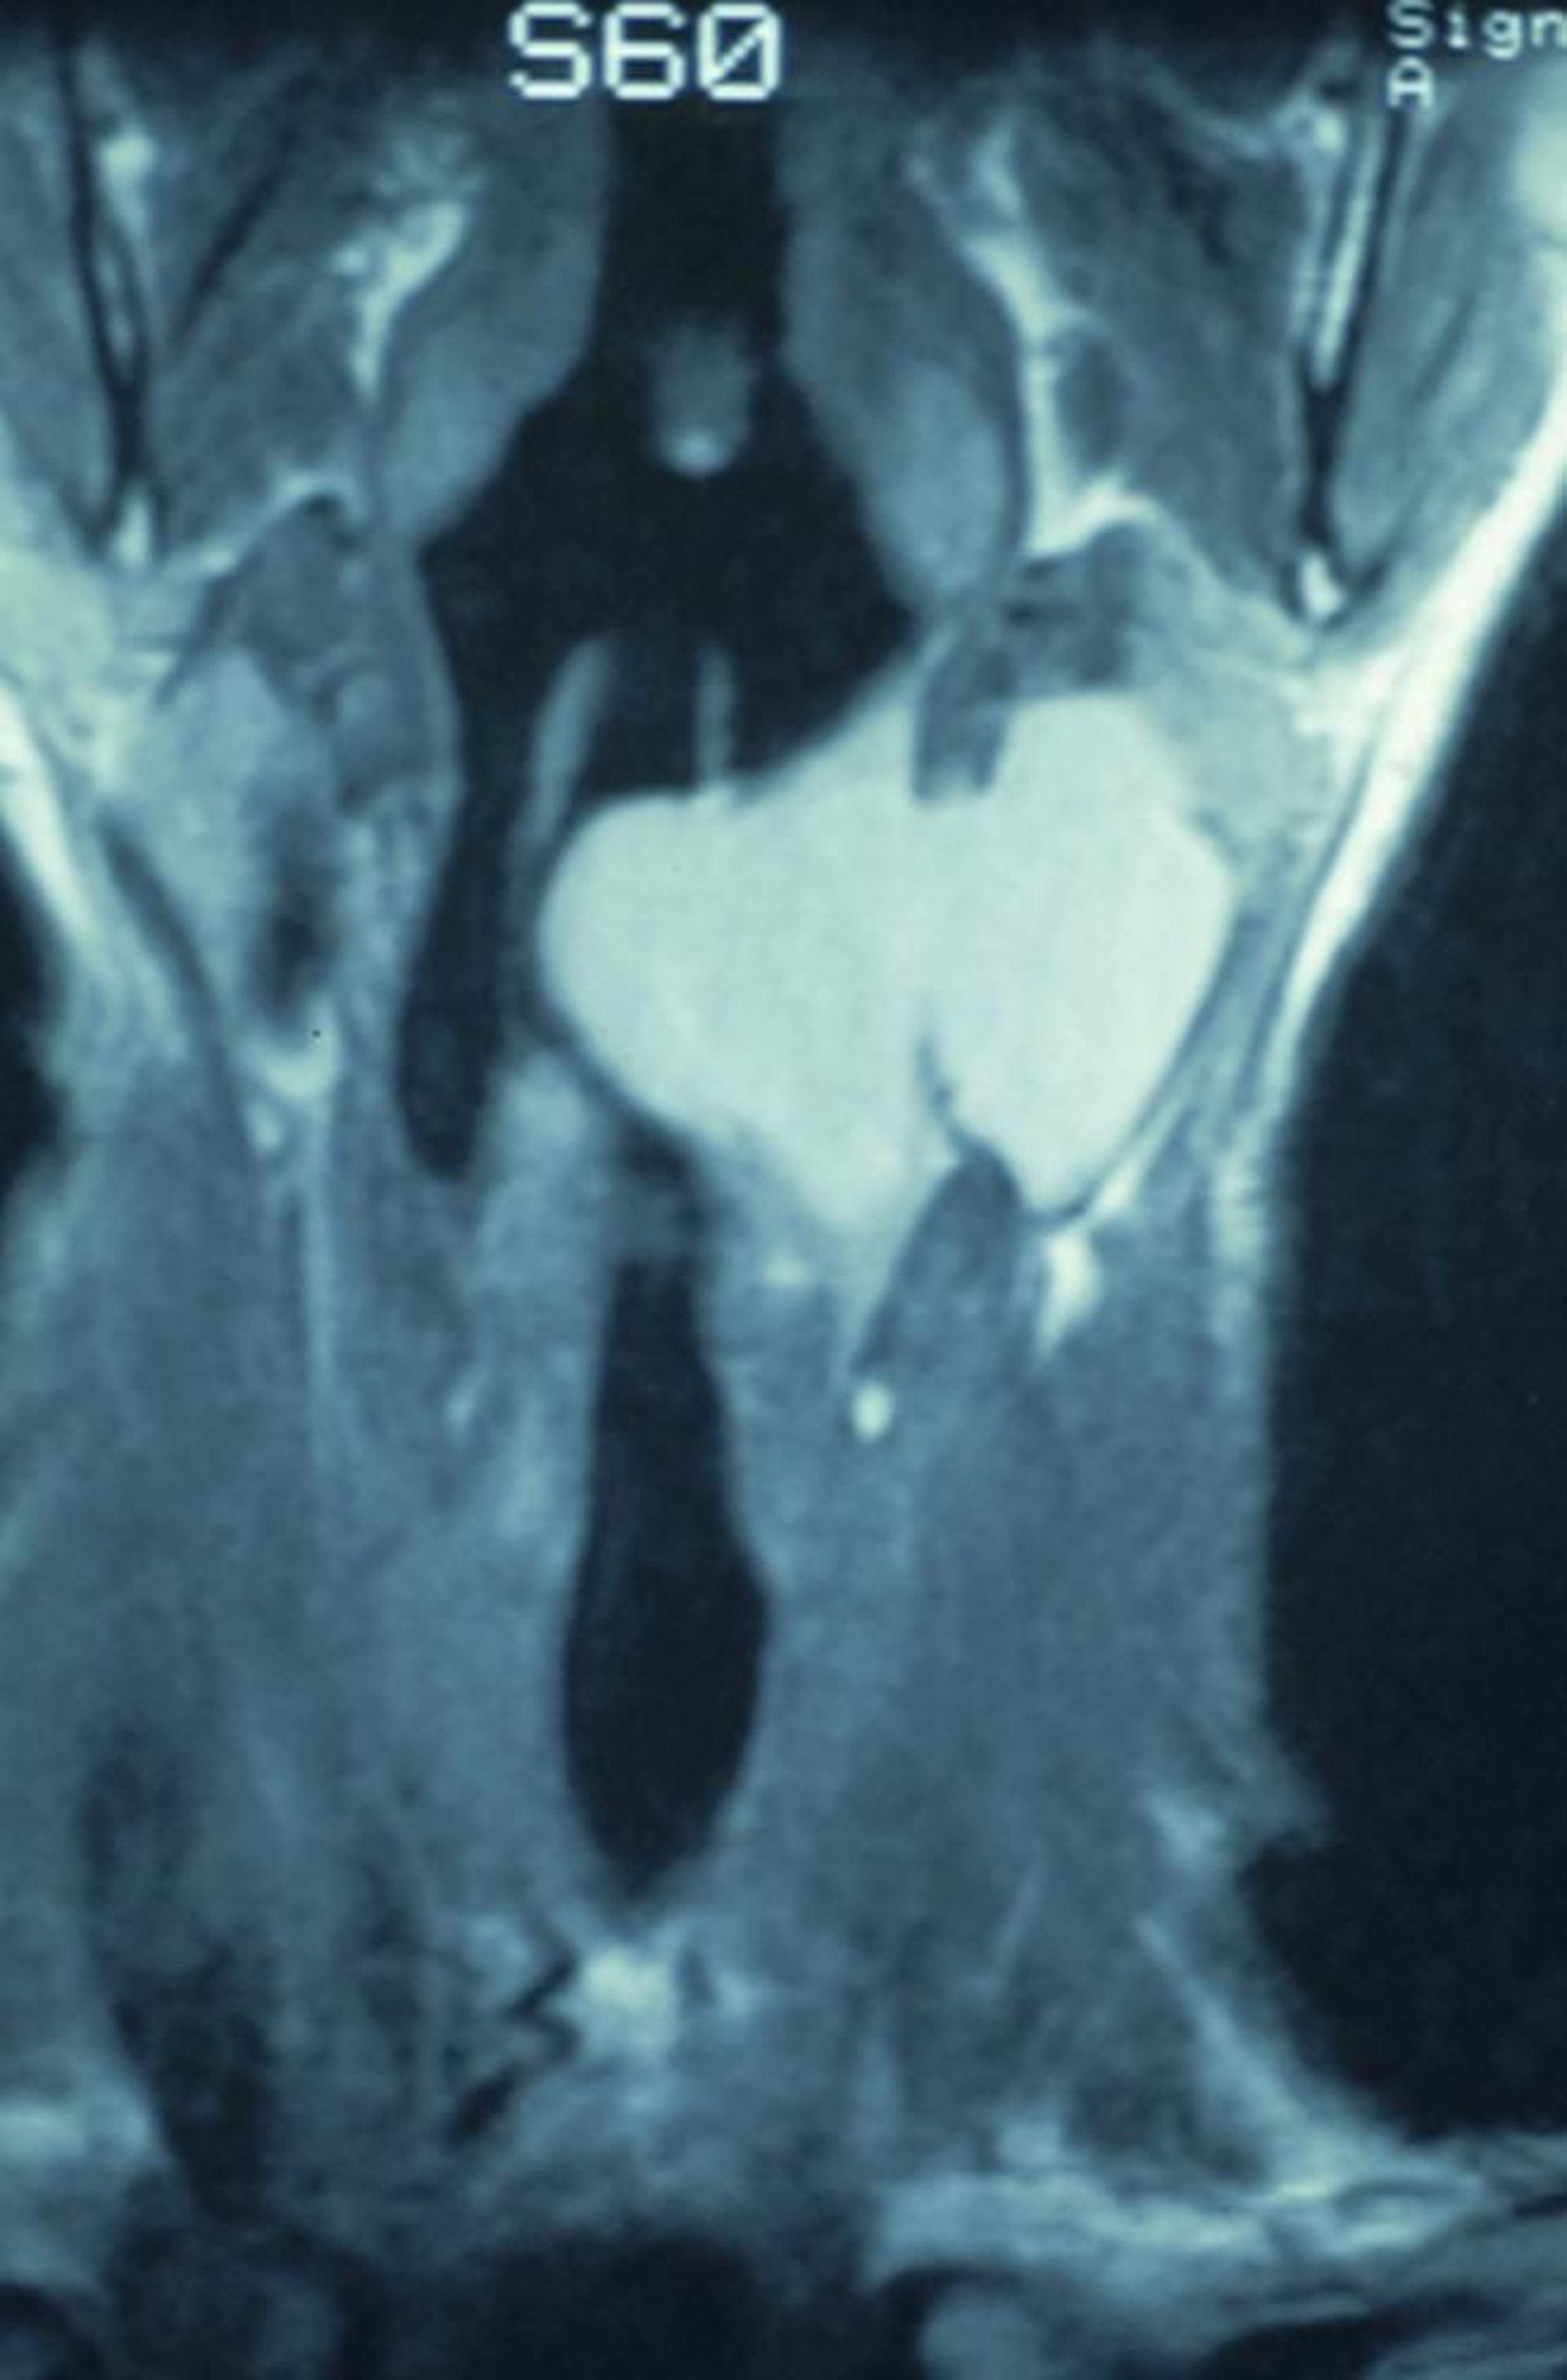

Esta RM coronal muestra un laringocele combinado que comienza dentro de la laringe y se extiende a través de la membrana tirohioidea, causando una masa en el cuello.

Image provided by Clarence T. Sasaki, MD.